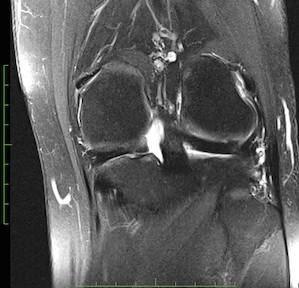

Figure 1 for case Meniscal ossicle

Figure 1